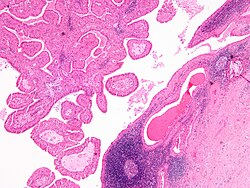

Microscopic

Features:

- Basal component.

- Basophilic cells - key feature.

- Usu. in nests.

- May be bilayered tubules or trabeculae.

- Large basophilic nucleus.

- Minimal-to-moderate eosinophilic cytoplasm.

- Stromal cells.

- Plump spindle cells without significant nuclear atypia - distinguishing feature.

- Stromal cell nuclei width ~= diameter RBC.

- Dense hyaline stroma.

- Tubular component.

- Within basal component, may be minimal.

- Lesion is encapsulated - key feature.